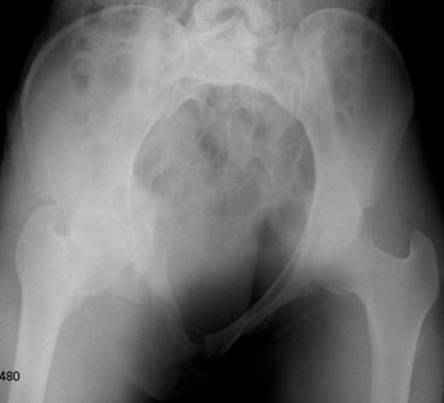

Re: перелом таза

Серия до- и послеоперационных снимков этой пациентки. Хотя бы post factum обсудить. Не знаю, что можно сделать с задними отделами стержневым аппаратом, но три крепких парня открытым путем с помощью "волшебных" слов еле-еле смогли отрепонировать - сзади все было очень ригидно!